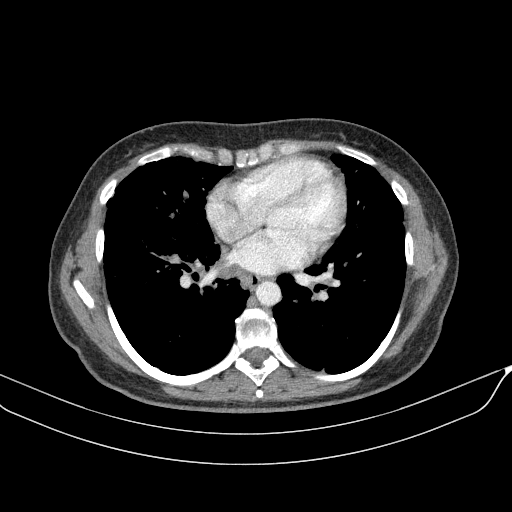

Generated VENOUS CT scan (A→B translation)

Full window (WL 1023.5, WW 4095 β†’ Low βˆ’1024, High +3071)